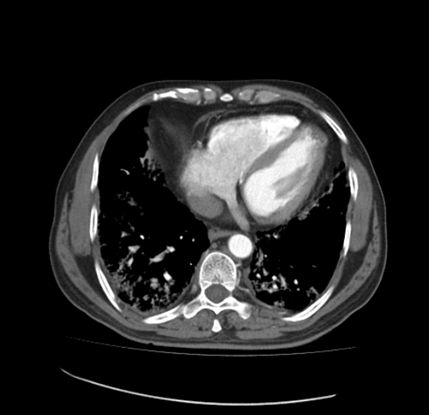

This image of the patient is with ground-glass opacities with the symptoms of milk short breath and fever. The figure 1 shows the day 1 imaging, in which the septal thickness is mild, as the symptoms grow to day 3, the thickness in found to be higher in the lungs of the patient, whereas a rise in ground-glass opacities is also observed.

Figure 1 Day 1 CT imaging.